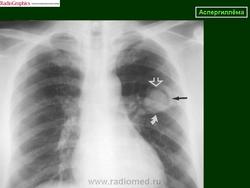

Аспергиллёма легких - находящийся в полости легкого или в бронхоэктазе подвижный конгломерат переплетенных аспергиллезных гиф, покрытый фибрином, слизью и клеточными элементами (по степени затемнения соответствует жидкости), располагающийся внутри овальной или сферической капсулы, отделяясь от нее воздушной прослойкой, с утолщением плевры.